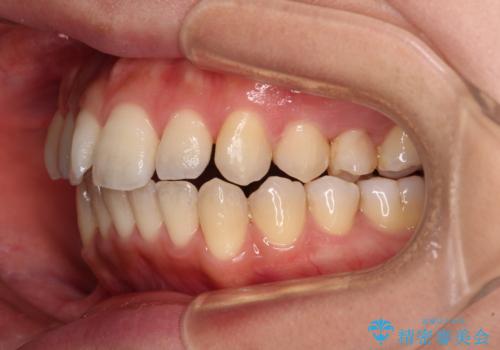

- 前歯のデコボコと咬み合わせを気にして来院された患者様です。

左上奥歯には乳歯が残存しており、後続永久歯は舌側に転位していました。

また、舌の突出癖の影響で上下前歯が接触していないオープンバイトとなっており、奥歯に負担のかかる咬み合わせとなっていました。

舌のトレーニングをしっかりと行ってくださり、前歯部のオープンバイトは大幅に改善されました。

もう少しでよりタイトに前歯が接触できそうでしたが、患者様がもう十分とのことで治療を終了しました。